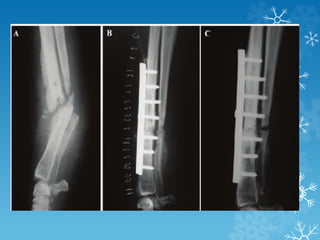

X-ray anteroposterior and lateral views with knee and ankle joints showing (a) Infected

nonunion lower tibia. Beads inserted (b) Ilizarov

fixator applied. Acute compression at nonunion site done gradually at low rate hence no angular

deformity at nonunion site despite an irregular

shaped defect. Simultaneous lengthening at upper level to equalize lengths (c) Union achieved

at distal end with good regenerate at proximal

corticotomy site and no limb length discrepancy

X-ray anteroposterior andlateral views with knee and ankle joints showing (a) Infected nonunion lower tibia. Beads inserted (b) Ilizarov fixator applied. Acute compression at nonunion site done gradually at low rate hence no angular deformity at nonunion site despite an irregular shaped defect. Simultaneous lengthening at upper level to equalize lengths (c) Union achieved at distal end with good regenerate at proximal corticotomy site and no limb length discrepancy